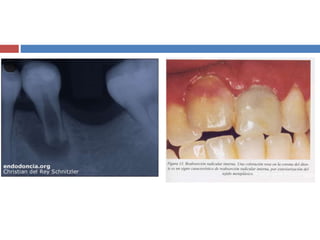

REABSORCIÓN INTERNA

 Transformación de la pulpa por tejido inflamatorio vascularizado con actividad dentinoclástica, que

reabsorbe las paredes dentinarias desde el centro hacia la periferia.

 La lesión es progresiva y puede llegar a perforar periodonto lateral produciéndose la necrosis del tejido

pulpar, convirtiéndose en una reabsorción mixta  interna-externa.

 La resorción dentaria interna (RDI) es también conocida como Hiperplasia Crónica Perforante de la

Pulpa, Granuloma Interno, Diente Rosado de Mummery.

 Tradicionalmente, las resorciones internas

se han asociado con procesos

inflamatorios crónicos en la pulpa. El

proceso resortivo se debe a la infección del

tejido pulpar en el conducto radicular. Se

cree que las resorciones internas pueden

ocurrir como cambios idiopáticos en

dientes sin restauraciones y sin caries. Las

radiografías revelan una zona radiolúcida

con aumento irregular del conducto

radicular.